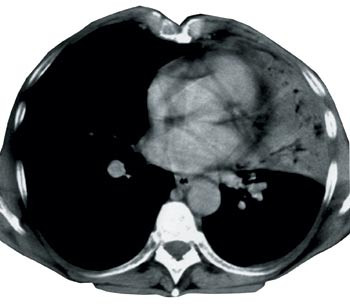

Kun 27 (63 %) av undersøkelsene hadde godkjent kvalitet. Dårlig kontrastfylling i karene i mediastinum eller mye bevegelsesartefakter på grunn av langsomt opptak var vanlige årsaker til ikke-godkjent kvalitet (fig 2). Verken de fire undersøkelsene der bare tumor var dekket av serien, eller de to utført helt uten intravenøst kontrastmiddel, ble godkjent. Kvaliteten på undersøkelsen ble likevel vurdert tilstrekkelig god for den aktuelle problemstillingen i tre av sju tilfeller der det på tross av infusjon ikke var optimal fylling av kontrast i mediastinale kar. Andel godkjente undersøkelser var større der spiral-CT var benyttet (22 av 25 undersøkelser, 88 %), sammenliknet med konvensjonell, aksial skanning (fem av 17 undersøkelser, 29 %). Av godkjente undersøkelser var en fra privat røntgeninstitutt, 11 fra lokal- og 15 fra sentral- eller regionsykehus. Av ikke-godkjente undersøkelser (n = 15) var to fra private røntgeninstitutt, 10 fra lokal- og tre fra sentral- eller regionsykehus.

En stor del av undersøkelsene i vår studie innfridde ikke kvalitetskravene i forhold til de anbefalinger som er gitt for denne undersøkelsen (6, 8, 9). Andel godkjente undersøkelser var klart lavere når konvensjonelle, aksiale skannere var benyttet enn når undersøkelsene var utført i mer moderne spiralskannere. Spiral (helikal)-CT ble introdusert allerede i 1990, og det er en rekke fordeler med denne type undersøkelse (10) – (12). Kort skannetid gjør det mulig for pasienten å holde pusten gjennom hele opptaket. Dermed blir bevegelsesartefakter redusert til et minimum. Mange institusjoner hadde ikke anskaffet spiral-CT i den aktuelle perioden, i gjennomsnitt åtte år etter at de første spiralskannerne ble introdusert.

God kontrastfylde er viktig for å påvise anatomiske strukturer og skjelne normalt fra patologisk vev. Kontrastmiddel kan være nødvendig for å separere vaskulære strukturer fra lymfeknuter, spesielt i hilusregionene (5). Undersøkelsestiden i en konvensjonell skanner er lang, og kontrastfyllingen i mediastinale kar kan derfor bli suboptimal. Dette skyldes som regel lang eksponeringstid for hvert snitt og forsinkelse ved bordforflytning. Denne forsinkelsen forekommer ikke ved spiralskanning, da bordforflytning og eksponering foregår samtidig.